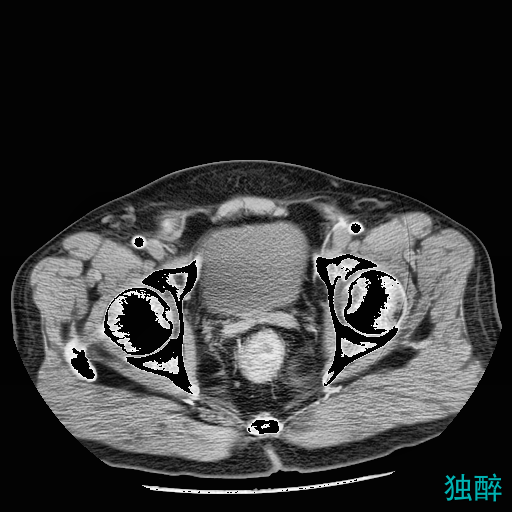

结果展示

经过处理后的CT图

医生画出的掩模图

预测出的掩模图

个别部分的棱角可能不太明显,但是整体形状以及位置是很相近的,而且我们只用了18个人做训练集,这个预测的模型用的是准确率到0.8的模型,经过参数的调整还能达到更高,大家可以再进行调试,一定可以得出更好的结果。